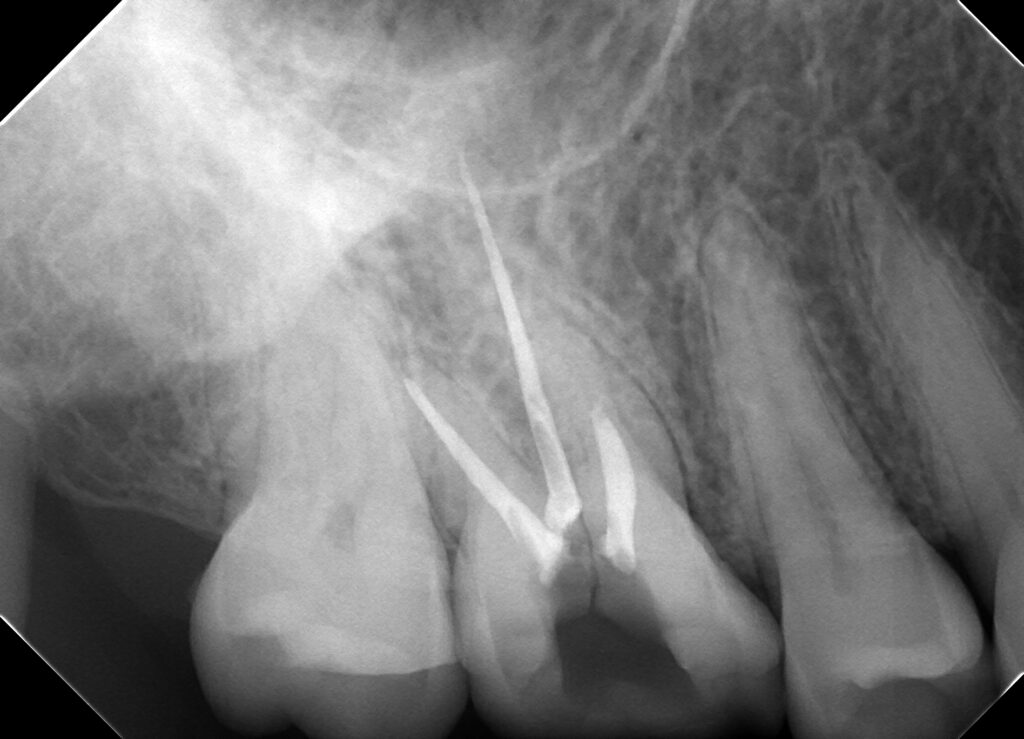

今回の写真は他院で歯が痛くて治療したけど違和感や噛んで痛いのが治らないということで来院されました。

口腔内見た状態では特におかしい所見はなかったのですがレントゲンをいろんな角度から撮影した結果真ん中に破折している所見が出てきました。

これが原因だろうとお話ししてここまで来てしまうと抜歯を行うことによる治療が第一選択になってしまうことを説明させてもらいました。

歯の破折は予見することが難しいのと診断が難しいのが特徴ですが無事原因がわかってよかった症例です。